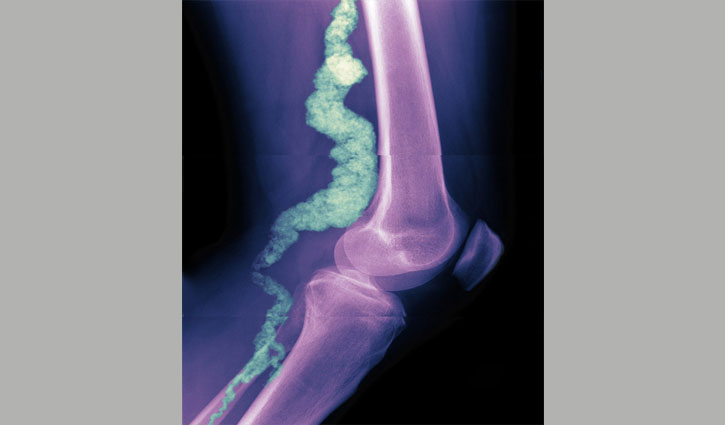

একজন এসিডিসি (সিডি৭৩ অভাবজনীত কারণে ধমনীজমাটবদ্ধ) রোগীর হাঁটুর এক্স-রে। একটি বিরল জমাটকরণ রোগ। ছবিতে দেখা যাচ্ছে রোগীর পায়ের নিচের অংশের প্রধান ধমনীতে রক্ত জমাট হয়ে আছে। এসিডিসি আক্রান্ত মানুষের কোমরের নিচে এবং হাত ও পায়ের জয়েন্টে বড় রক্তনালী সমূহের মধ্যে ক্যালিসিয়াম তৈরি হয়। এ রোগের উপসর্গ হচ্ছে- হাত, পা ও নিতম্বে খিল লাগা এবং ক্রমশ ব্যথা বাড়তে থাকা।